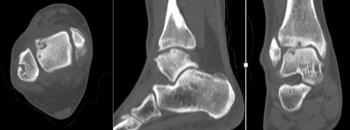

After a lengthy discussion, we ordered a computed tomography (CT) scan. Although she obtained relief from arthroscopy, it was short-lived. Other options discussed included autograft cartilage transfer and larger open bulk allograft replacement. The CT scan revealed a large portion of the lateral talar dome was involved. The cystic areas had grown in size and number to include much of the lateral shoulder. The lesion was uncontained and encompassed much of the anterior-posterior depth of the talus.

We presented the option of a patient-specific partial talar replacement with a plan to resect and replace the entire lateral shoulder. As part of the design process, the implant had custom cut guides that would sit on the talar neck, temporarily secured in place with smooth wires. This guide would then correlate with the final implants to ensure the appropriate amount of bone removal and allow more accurate bone resection. In addition, the design incorporated two stems in the final implant to add stability and fixation surface area. Three sizes of implant allowed intra-operative flexibility.